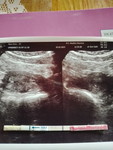

Tgl 21 maret aku pndrahan kecil tapi cuma 1 hari apa kah akan baik baik saja

usg bun, cari tau

usg